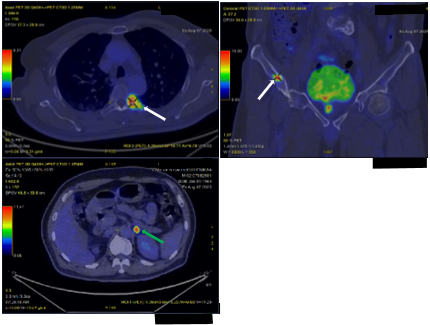

Sau đó, bệnh nhân được bổ sung các xét nghiệm đánh giá toàn thân. Kết quả phim chụp cắt lớp vi tính ngực và bụng cho thấy, không chỉ có khối u ở tuyến tiền liệt mà bệnh nhân còn có nhiều khối u khác ở phổi (Hình 2), tuyến thượng thận (Hình 3) và xương (Hình 4).

Hình 2: Hình ảnh 02 khối u bờ đa cung ở nhu mô thùy giữa phổi phải, dính vào màng phổi trung thất (mũi tên đỏ) kèm nhiều nốt đặc nhỏ rải rác nhu mô phổi hai bên (mũi tên vàng) gợi ý tổn thương thứ phát.

Hình 3: Hình ảnh dày tuyến thượng thận phải tạo nốt có kích thước 19 x 17 mm (mũi tên đỏ).

Hình 4: Hình ảnh xạ hình xương cho thấy các ổ tăng hoạt độ phóng xạ nhiều vị trí tại xương cột sống, xương đòn phải, xương chậu phải, cung sau xương sườn 2, 5 bên trái, đầu dưới xương cẳng tay bên phải, đầu trên xương đùi phải hướng đến tổn thương thứ phát.